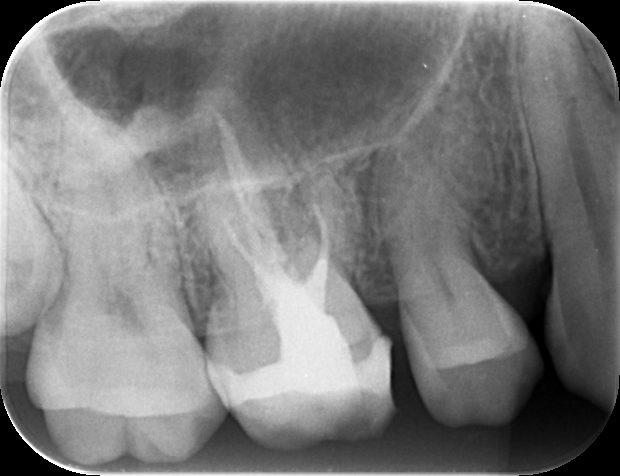

症例 上顎第一大臼歯抜髄処置 2025.10.02 【主訴】 上顎第一大臼歯部の自発痛出現にて、歯内療法専門医受診希望 【背景】 上顎第一大臼歯部に自発痛出現し、根管形態の複雑さから、歯内療法専門医にて治療を示唆 診査診断後、通報に従い、一回の処置で歯内療法及び支台歯築造まで終了し、 仮歯にて1週間ほど経過観察し、セラミック修復に至る 治療前 治療後 セラミック咬合面 セラミック頬側面 【考察】 元々、食いしばり傾向が強く認められる患者であり、メタルインレーにて咬合面をほぼ覆う形態で修復されていた この場合、咬合力コントロールされていない症例では、歯にヒビ(クラック)が生じ、噛むと痛いという訴えや、 神経に達する症状が突然出現するケースも散見される 神経が温存される症例でも、全体的にクラウン形態で修復することが望ましい 【治療回数】 歯内療法 1回 歯冠修復 2回 【治療担当医】 歯内療法 野田哲朗 歯冠修復 白土 州 この記事のタイトルとURLをコピーする